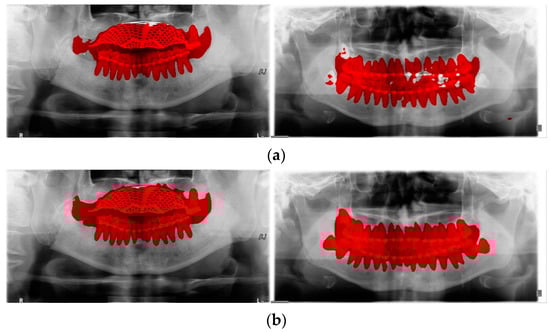

YOLO, Mask-R-CNN, and U-Net use different data-segmentation methods when constructing the training data. First, the mandibular fracture diagnosis module using Son et al.’s LAT YOLOv4 has a good diagnostic ability for fracture positions; however, it has a high undetected rate because it does not accurately distinguish fracture shapes and expresses fracture areas in the form of boxes. This module shows the diagnostic performance of precision of 97%, recall of 79%, and F1 score of 88%. In particular, fractures in the symphysis, body, angle, and ramus tend to be distributed in the middle of the mandible, and undiagnosed detection errors increase owing to irregular fracture shapes and overlapping location information. The advantage of location information is weakened; there is the possibility of a case where a fracture that is visible to the naked eye cannot be detected (Figure 3b). Therefore, additional applications such as Mask R-CNN, which is another object detection deep learning, and U-Net, which is used for medical image region segmentation, are needed to improve detection capabilities, especially recall scores representing undiagnosed performance in existing studies.

Figure 3.

The result of mandibular fracture detection: (a) diagnosis by oral and maxillofacial radiologist, (b) by LAT YOLOv4 module (with red boxes), (c) by Mask R-CNN (with colored polygons and boxes), and (d) by U-Net.

Unlike YOLO learning data consisting only of box coordinates and class information, Mask R-CNN requires the designation of a polygon-type learning region in the fracture region for the construction of a mandibular fracture learning dataset. However, in the case of shear fractures without gaps or dislocation fractures occurring in the condyle region, it was difficult to express the training data region using Mask R-CNN. Because these specific fracture regions cannot be drawn in closed polygon form, fracture regions are represented and trained in a box or simple form, such as YOLO learning data. In this case, for comparison with the results of the LAT YOLOv4 module [], training was performed with the same class structure on the same training data, and the detection results in the same test data were 57% precision, 70% recall, and 63% F1 scores. The fracture shape of the condyle region is not properly expressed, which leads to an error in judgment owing to the fracture shape, and the error detection between teeth is also recognized as a fracture in the panoramic image, resulting in a lower precision score (Figure 3c).

For U-Net training, a training dataset labeled according to the shape of the fracture is constructed. This makes it easy to generate U-Net training datasets of fracture sites with complex spacing. However, shear fractures or displaced fractures are difficult to be labeled. Therefore, in the case of shear fractures, the parts which are visible even with solid and crack lines in the shear fractures were labeled as much as possible. But the displaced fractures were not labeled because it adversely affected the fracture detection accuracy during U-Net training. Additionally, when segmentation and labeling are performed differently from complex fracture shapes, it adversely affects the training process and reduces mandibular fracture detection performance. Figure 3d confirms that U-Net shows good segmentation performance for general fracture types but U-Net shows poor segmentation performance for dislocated fractures in the condyle region because U-Net was not trained in condyle region. Therefore, U-Net is advantageous for learning the rest of the fracture areas except for some of the severe shear and displaced fractures.